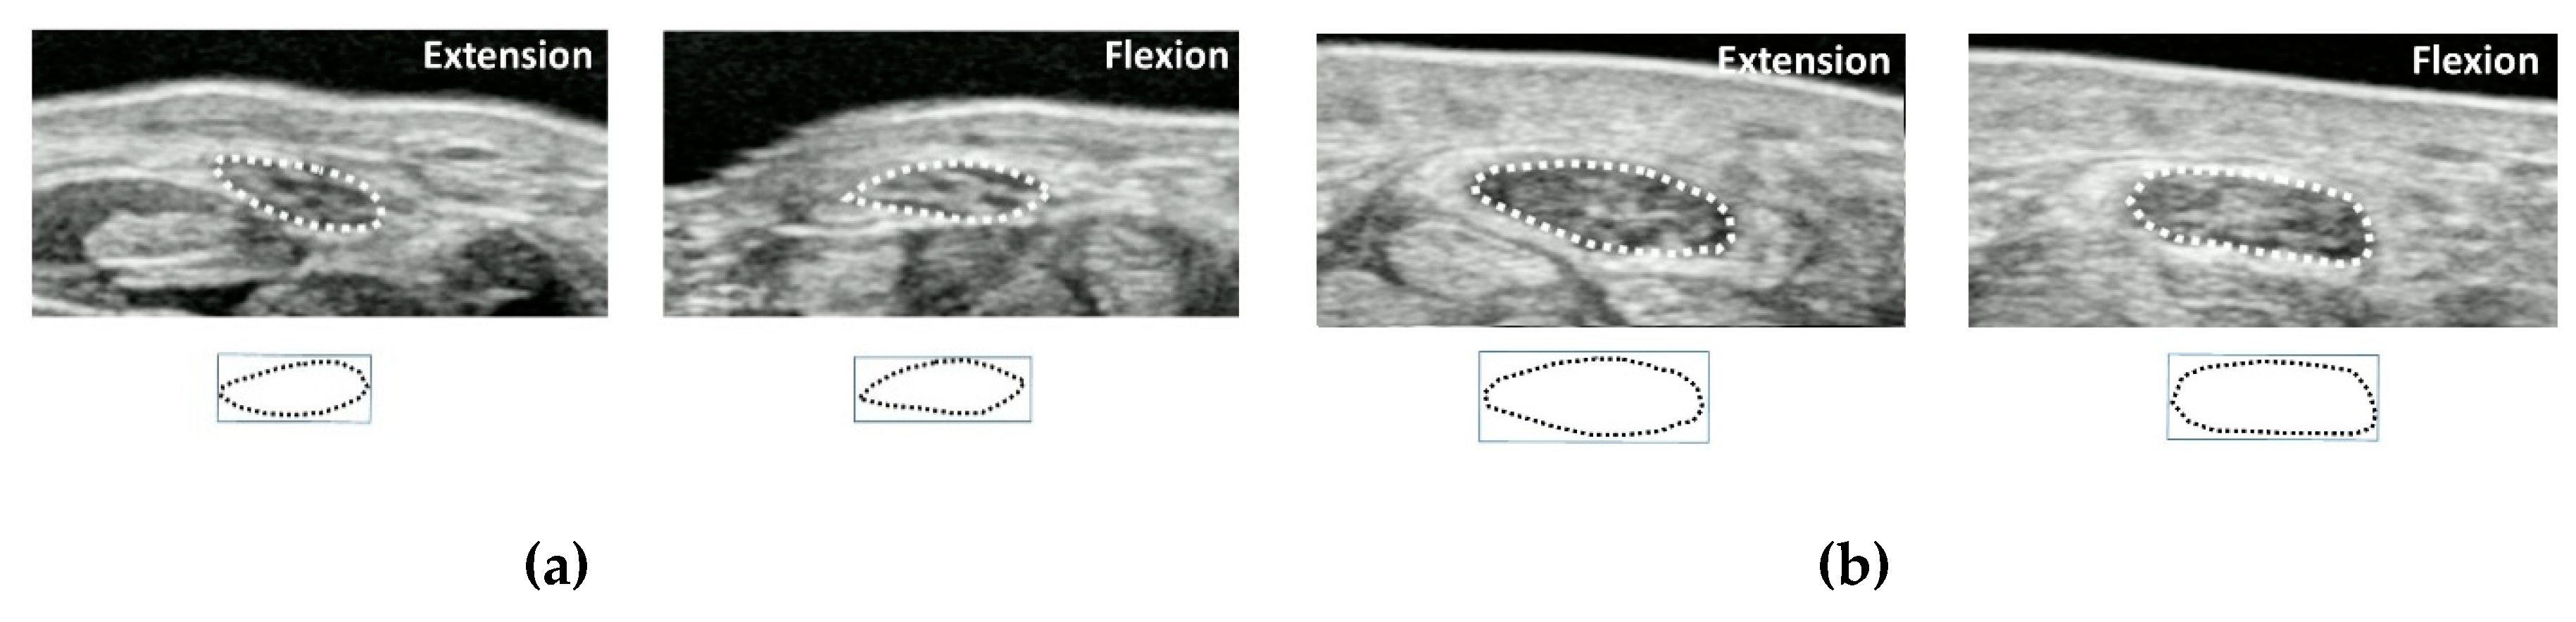

In order to clarify the morphological changes and displacements of the median nerve during flexor tendon sliding in CTS patients, cross-sectional dynamic analysis was introduced [45,46,47]. In this method, the transducer is placed parallel to the wrist crease at the proximal part of the carpal tunnel (Figure 3). The subject is instructed to imitate a grasping motion from finger extension to finger flexion (until the fingertip touches the palm) while recording the ultrasonic dynamic image of the tendons, median nerve, and SSCT. The final position of each extension and flexion position is the target of image evaluation, and the morphology and displacements of the median nerve are traced. The median nerve area, circumference, aspect ratio, and circularity are evaluated. Circularity is a feature that measures the complexity of a shape based on area and perimeter, and is defined as (square of median nerve circumference)/(median nerve area × 4π). Therefore, in the case of a perfect circle, the degree of circularity becomes one. Each parameter was compared between healthy subjects and CTS patients and between finger extension and flexion. For both finger extension and flexion positions, there were significant differences between healthy subjects and CTS patients in the median nerve area, circumference, and circularity. As for the deformation patterns in the healthy subjects, when the finger flexed, the aspect ratio decreased and the circularity increased. On the other hand, the aspect ratio increased and the circularity decreased in the CTS patients during finger flexion [46,47,48]. It was found that healthy subjects show morphological changes such that nerves are flattened when the fingers are flexed but become more like a circle in CTS patients.

These facts show that in a healthy person the median nerve can be morphologically deformed by tendon motion accompanying finger motion. The change in the cross-sectional area is also considered to be a movement of the median nerve in the longitudinal direction. On the other hand, in CTS patients it can be seen that the morphological changes of the median nerve associated with finger movement are small. Dynamic ultrasound can detect these changes of mobility and flexibility of median nerve in the pathological conditions of CTS.

Figure 3. An example image of the median nerve shape in finger extension and flexion positions. (a) Healthy subjects, (b) carpal tunnel syndrome (CTS)patients. Reprinted from [48].